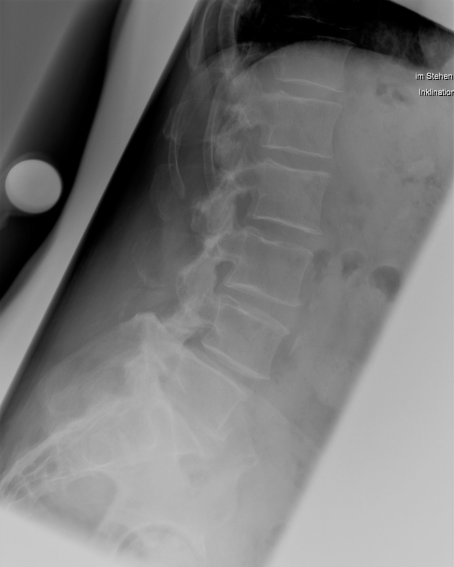

Wirbelgleiten (Spondylolisthese)

Beim Wirbelgleiten (Spondylolisthese) verschieben sich einzelne Wirbelkörper zueinander. Dies kann durch Abnutzung oder angeborene Verknöcherungsstörungen bedingt sein und sowohl in hohem Alter als auch in der Jugend zu Beschwerden führen. Das Wirbelgleiten kann durch die damit verbundene Instabilität zu Rückenschmerzen oder auch durch Verengungen an Wirbelkanal und Nervenaustrittslöchern zu schmerzhafter Ausstrahlung in die Beine führen. Sollten krankengymnastische Behandlungen oder minimalinvasive Therapiemöglichkeiten, keine Beschwerdelinderung erreichen, so wird in einer Operation zunächst das regelrechte Profil der Wirbelsäule wieder hergestellt und anschließend stabilisiert (Repositionsspondylodese). Die zwischen den Wirbelkörpern liegende Bandscheibe ist in der Regel zerstört und wird durch einen Platzhalter ersetzt. Diese Maßnahme kann von vorne, von der Seite oder von hinten am Wirbelkanal vorbei durchgeführt werden, sie ist wesentlich zur Festigung der Versteifung.

Beispiel Wirbelgleiten